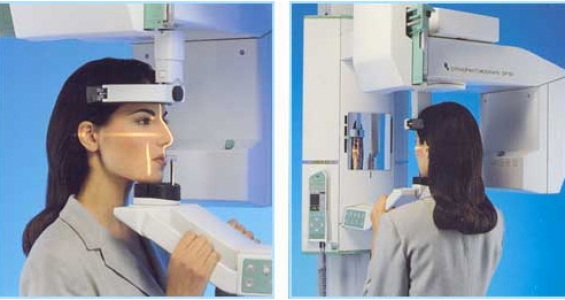

Ortopantomografia digitale: è una vera e propria immagine bidimensionale della bocca che permette di studiare le due arcate dentali, l’osso mandibolare e mascellare, le articolazioni e i tessuti gengivali. I vantaggi dell’OPT digitale sono la bassa emissioni di radiazioni e la possibilità di avere immediatamente l’immagine disponibile. L’OPT digitale consente la valutazione complessiva delle strutture ossee e dentali con valutazioni specifiche nell’ambito di vari settori specialistici.